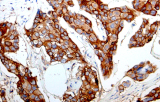

A imunohistoquímica (IHQ) com anticorpos primários CE/IVD é essencial para o diagnóstico e classificação precisos de malignidades ginecológicas e mamárias. Estes anticorpos permitem a deteção precisa de marcadores tumorais e proteínas celulares, apoiando o diagnóstico diferencial e guiando estratégias terapêuticas personalizadas.

Estudos recentes destacam o valor diagnóstico das proteínas do complexo SWI/SNF, particularmente ARID1B, na identificação de malignidades ginecológicas desdiferenciadas e indiferenciadas – tumores agressivos com mau prognóstico. A IHQ de ARID1B oferece elevada especificidade e está cada vez mais integrada em painéis diagnósticos para melhorar a precisão. Painéis com marcadores adicionais também apoiam a diferenciação de sarcomas uterinos, aumentando a exatidão diagnóstica. Evidência emergente sugere que ARID1B pode representar um alvo terapêutico potencial no carcinoma ovárico de células claras, embora as aplicações clínicas permaneçam em fase investigacional.